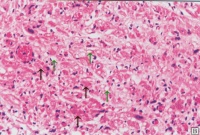

克山病的主要病变是心肌实质的变性、

坏死和纤维化交织在一起心脏呈肌原性普遍扩张,心壁通常不增厚。20%的患者可见附壁血栓及肺、脑、肾、末梢血管的栓塞。光镜可见心肌变性和坏死。心肌变形呈弥漫性,坏死呈灶状分布。病变通常以左心室及室间隔部为重,右心室较轻。点镜主要表现为线粒性肿胀、增生和嵴及肌原纤维破坏。